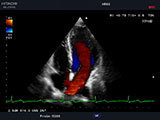

心臓超音波検査(心エコー図検査)

常盤台(ときわ台))近くの夜間救急対応の犬猫専門動物病院上板橋リズ犬猫病院の心臓超音波検査画像

心臓超音波検査

当院では心臓超音波検査(心エコー図検査)が実施可能です。レントゲン検査ではわからないリアルタイムの心臓の動きを診断します。この検査では、診断名(僧帽弁閉鎖不全症、三尖弁閉鎖不全症、肺高血圧症、猫の心筋症など)がわかるだけでなく、その動物にどんな薬をどのくらい処方すればよいのかもわかります。

当院ではレントゲン検査のみで診断名や薬の処方をすることはありません。レントゲン検査のみで診断や薬を処方してしまうことは間違った治療であったり、病気を過少または過大評価することにつながります。しっかり心臓超音波検査をすることにより飼い主様にも納得していだける病気のご説明や治療が可能です。